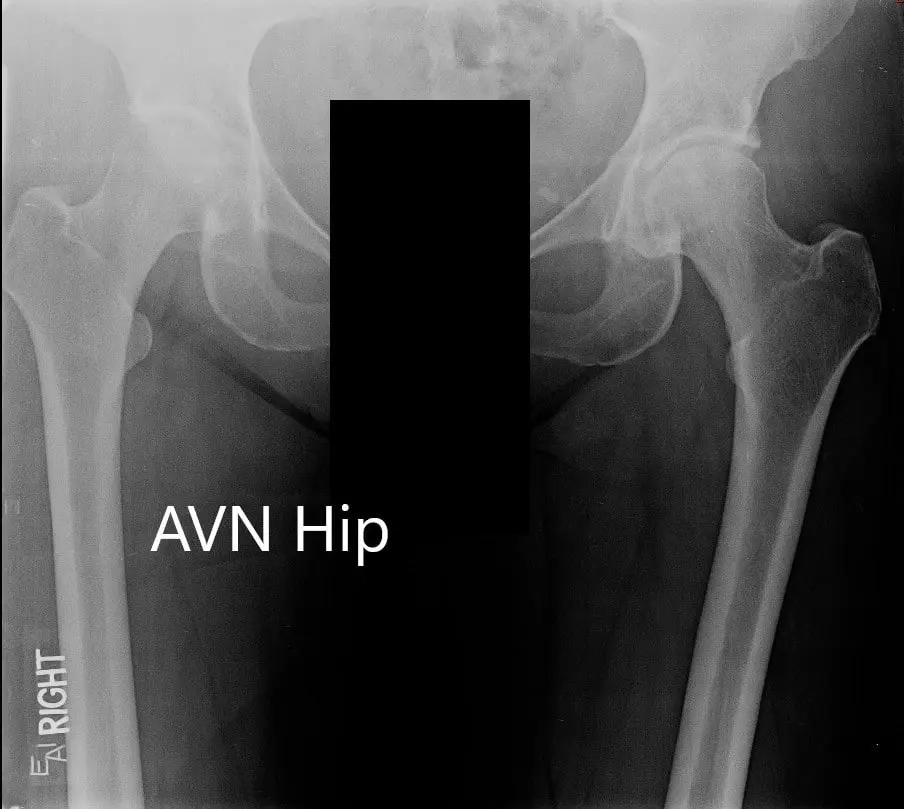

Imaging revealed osteoarthritic changes of the left hip with an AVN lesion that involves 60% of the femoral head. An MRI was obtained which revealed left femoral head avascular necrosis without overt subchondral collapse.

X-ray showing the AP view of the pelvis with both hip joints

X-ray showing the AP and frog-legged lateral views of the left hip joint